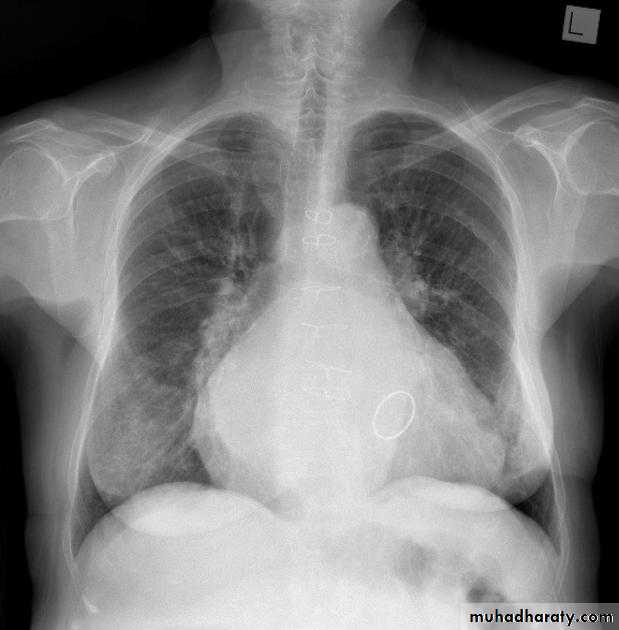

Pericardial effusions occur when fluid collects in the pericardial space (a normal pericardial sac contains approximately 30-50 mL of fluid).

adiographic features

Plain radiograph

a very small pericardial effusion can be occult on plain film

there can be globular enlargement of the cardiac shadow giving a water bottle configuration known as Globe shape heart or pumpkin shape heart .

Pericardial effusion